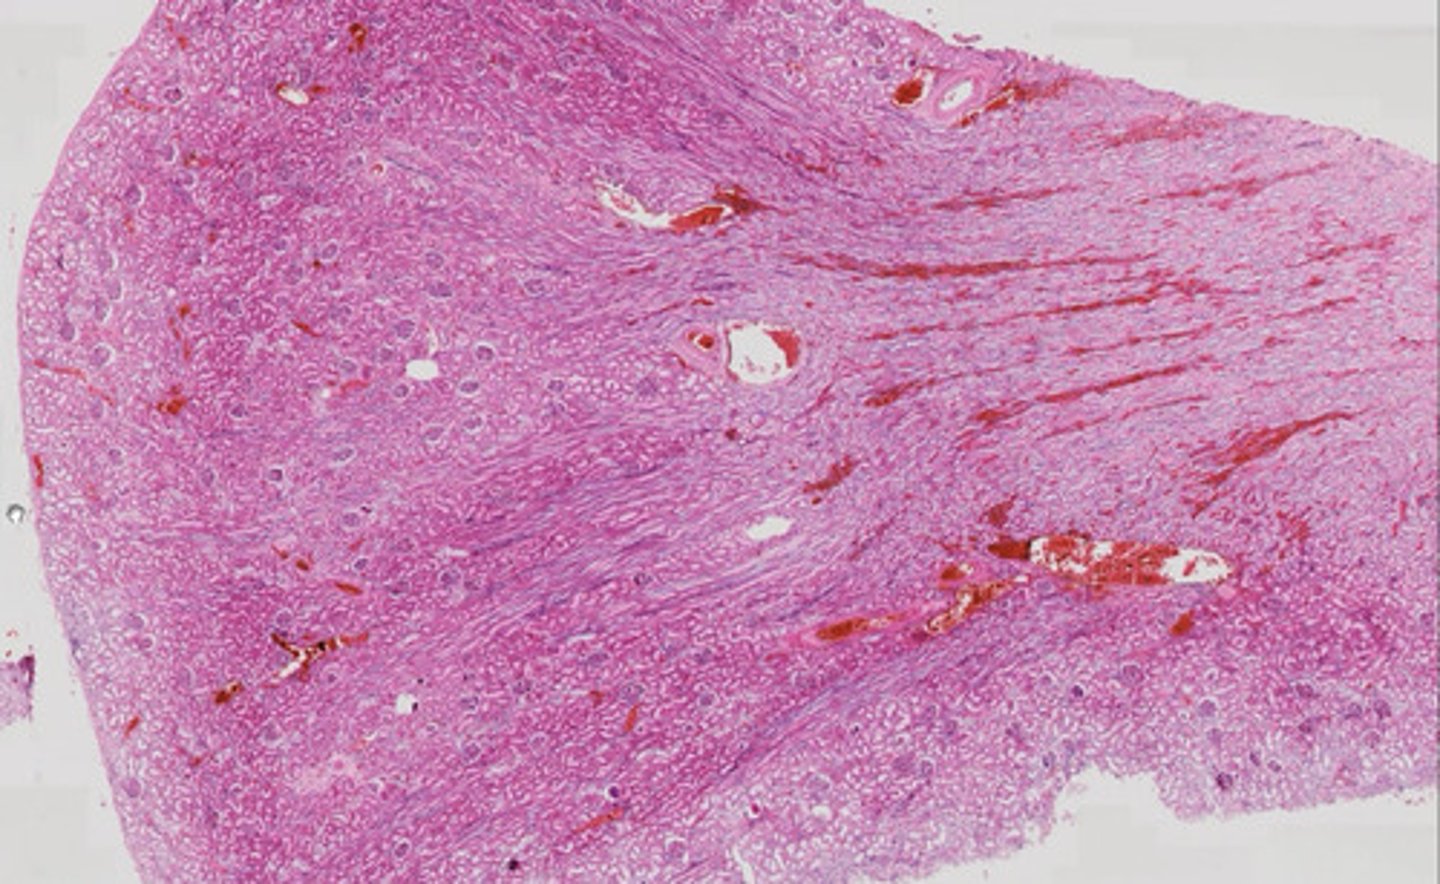

Gruczoł krokowy (met. Mallory)